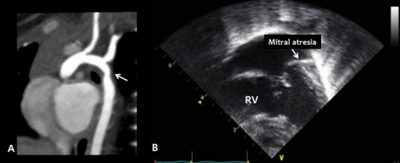

Congenital cardiac defects - a) coarctation of the aorta -arrow b) mitral valve atresia

A consensus on clinical diagnostic criteria for Kabuki syndrome (KS) was defined in December 2018 by an international group of experts.[12] The authors propose that a definitive diagnosis can be made in an individual of any age with a history of infantile hypotonia, developmental delay and/or intellectual disability, and one or both of the following major criteria: (1) a pathogenic or likely pathogenic variant in KMT2D or KDM6A; and (2) typical dysmorphic features (defined below) at some point of life. Typical dysmorphic features include long palpebral fissures with eversion of the lateral third of the lower eyelid and two or more of the following: (1) arched and broad eyebrows with the lateral third displaying notching or sparseness; (2) short columella with depressed nasal tip; (3) large, prominent or cupped ears; and (4) persistent fingertip pads. Further criteria for a probable and possible diagnosis, including a table of suggestive clinical features, were included in the publication.[12]